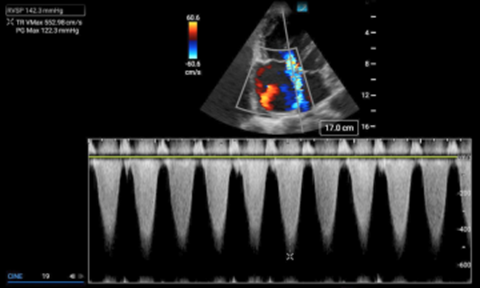

The right ventricular systolic pressure (RVSP) determined by echocardiography can approximate the pulmonary artery systolic pressure (assuming a normal pulmonic valve). Determining this value is predicated on the ability to measure the velocity of the tricuspid regurgitant jet in an apical four chamber view. To obtain this value, the tricuspid regurgitant jet is first identified in an apical four chamber view (A4C) using color doppler. The eccentric jet shown in Figure 1 highlights the importance of first localizing it with color doppler. Then a continuous wave (CW) doppler line is placed through that jet with the focal zone (diamond) in or near the vena contracta (the thinnest part of the jet close to the valve). The resulting wave form should demonstrate repeating downward parabolas. (Figure 1) Increasing the doppler scale, and adjusting the baseline upwards, may be necessary to avoid aliasing for these high velocity cases. The pressure gradient is then extrapolated by using a simplified Bernoulli equation. In the case of this patient, the velocity measures 5.53 m/s, so the pressure gradient (PG) is about 122mmHg (normal would be zero to trace regurgitation). In cases where the diagnosis of PAH is known, comparing the patient’s historic RVSP value to that on presentation, can be helpful.

Figure 1. Continuous wave doppler measuring the maximum velocity of the tricuspid regurgitant jet (TR Vmax).